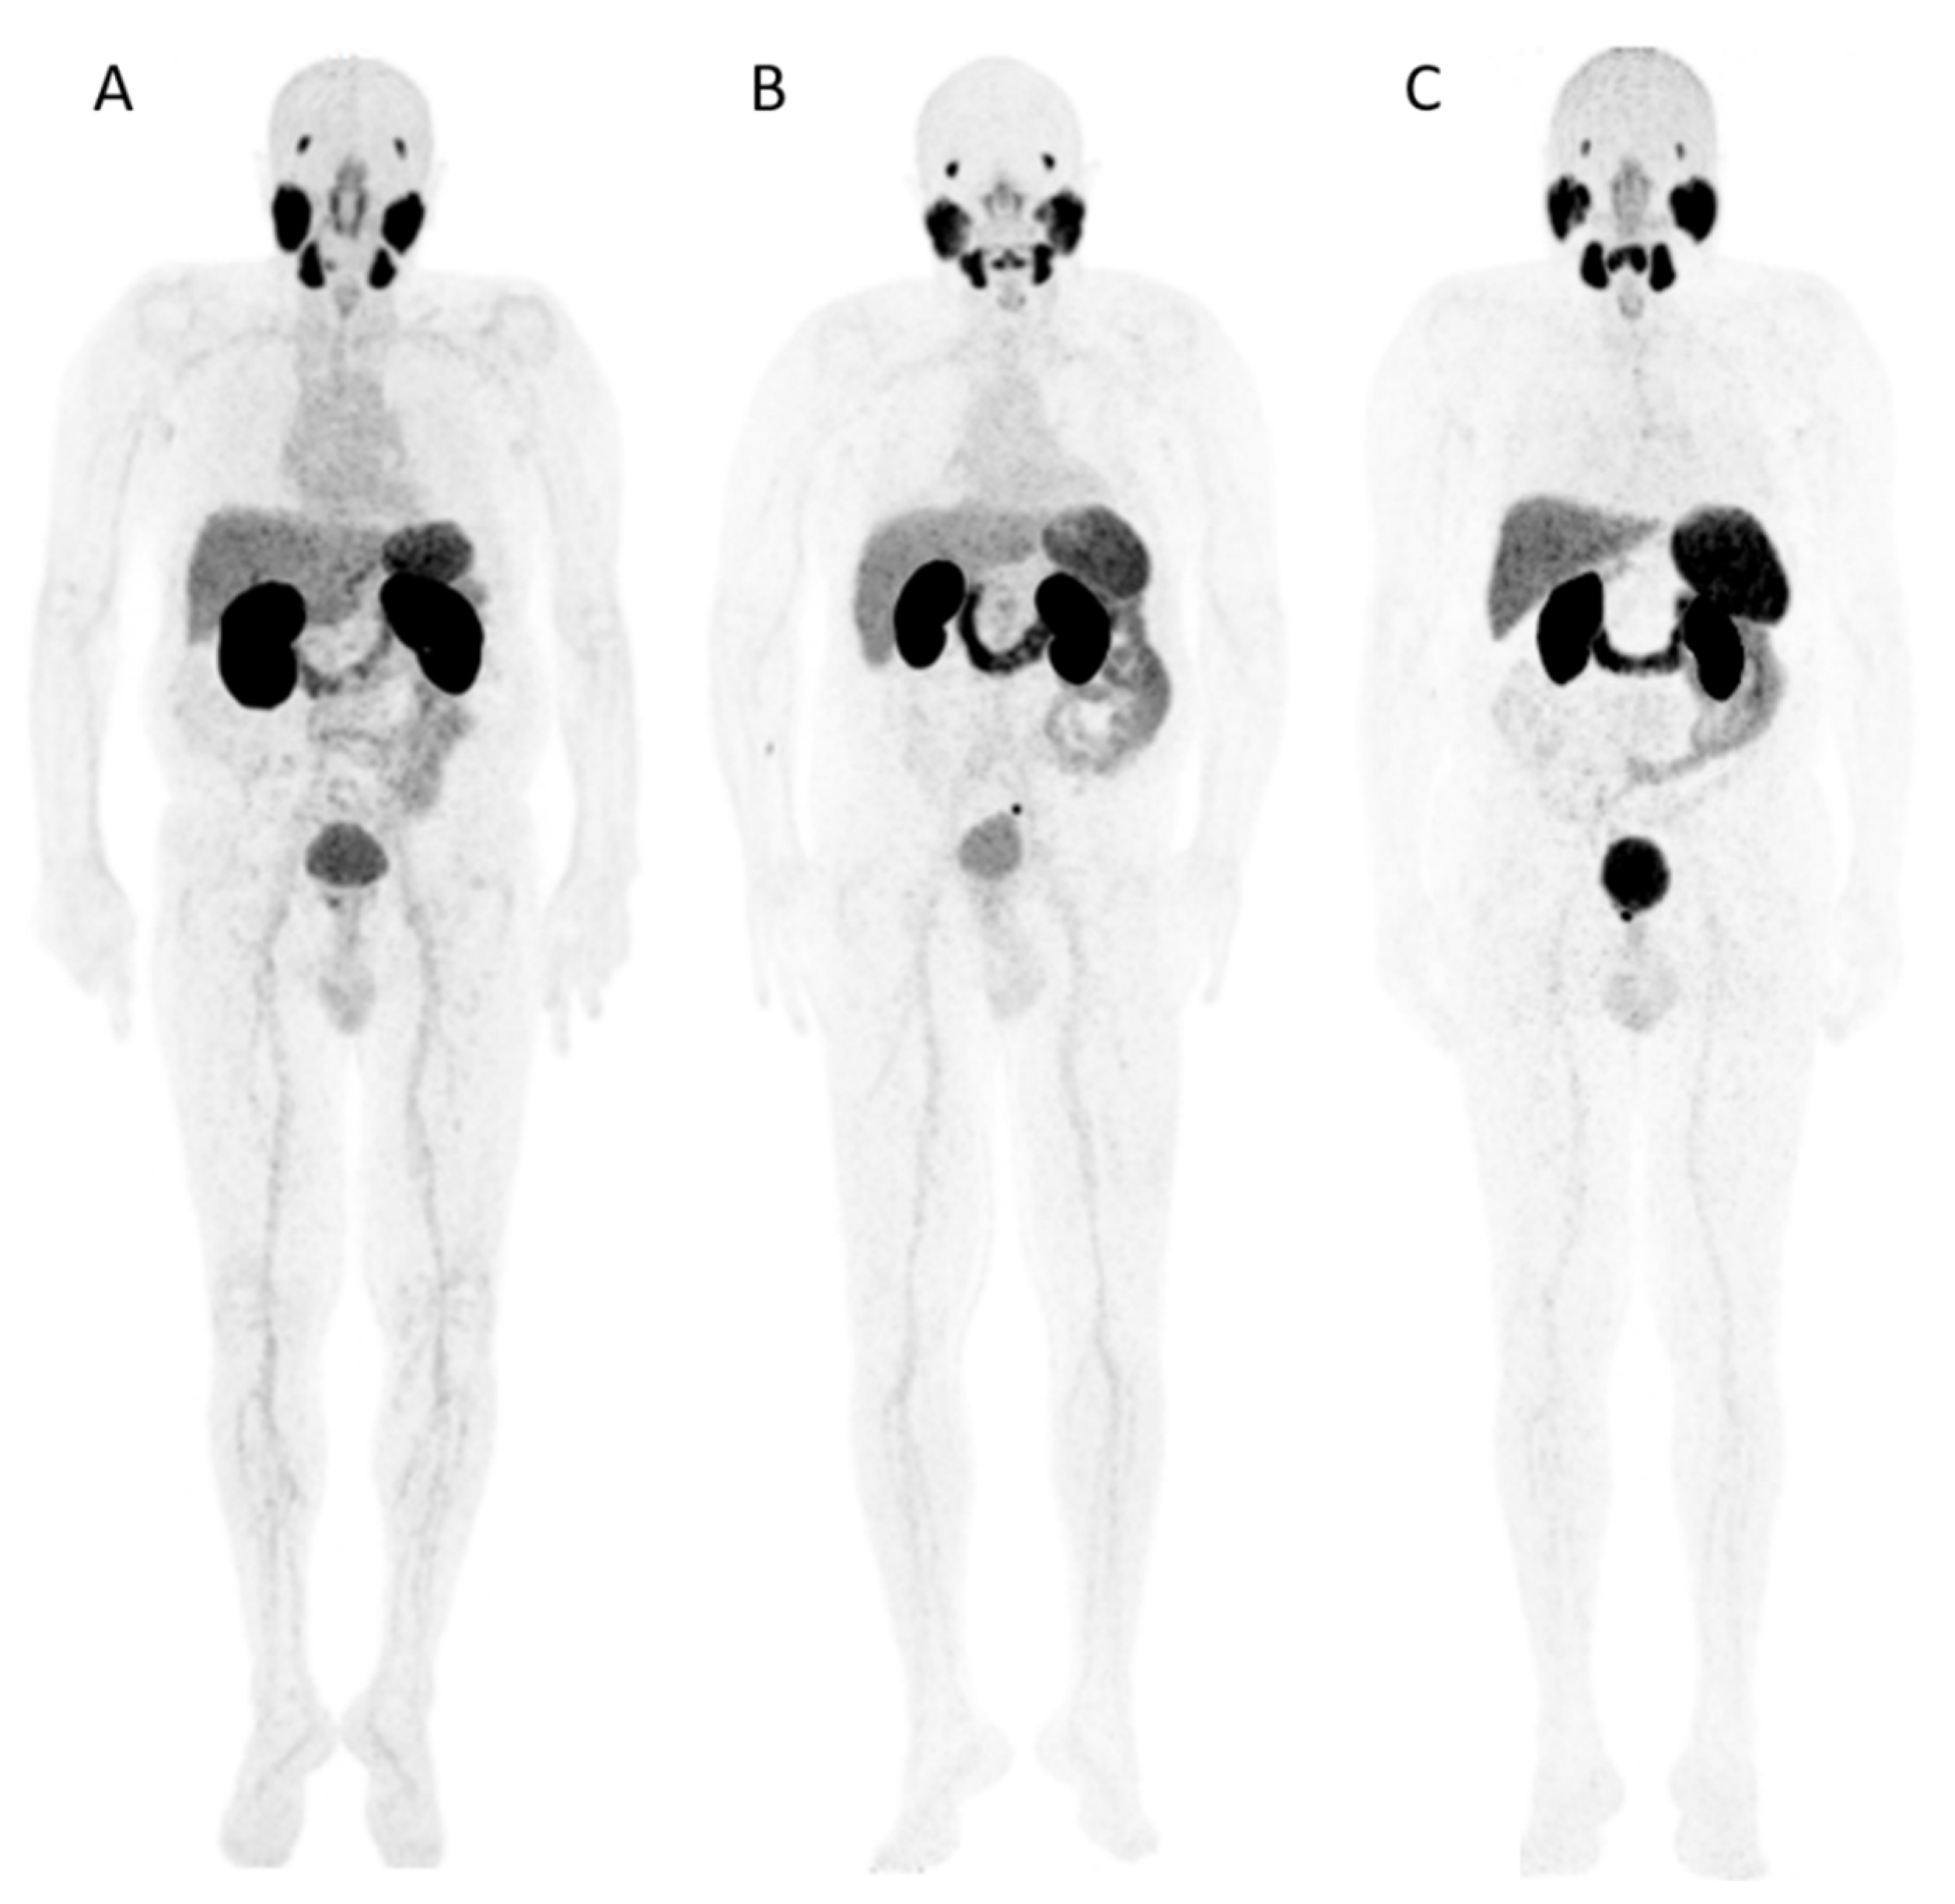

2.2. Distribution